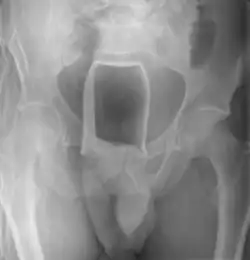

Обычно делают несколько рентгеновских снимков, чтобы точно определить место нахождения инородного тела. Инородные тела из малоконтрастного материала (например, пластика) могут потребовать ультразвукового исследования или компьютерной томографии.[28] Магнитно-резонансная томография противопоказана, особенно если неизвестен материал инородного тела. Инородные тела прямой кишки могут проникать глубоко в толстую кишку, при определённых обстоятельствах вплоть до правого изгиба ободочной кишки.[9]

| Стеклянная бутылка | Биопсийные щипцы | Общая | [32] |